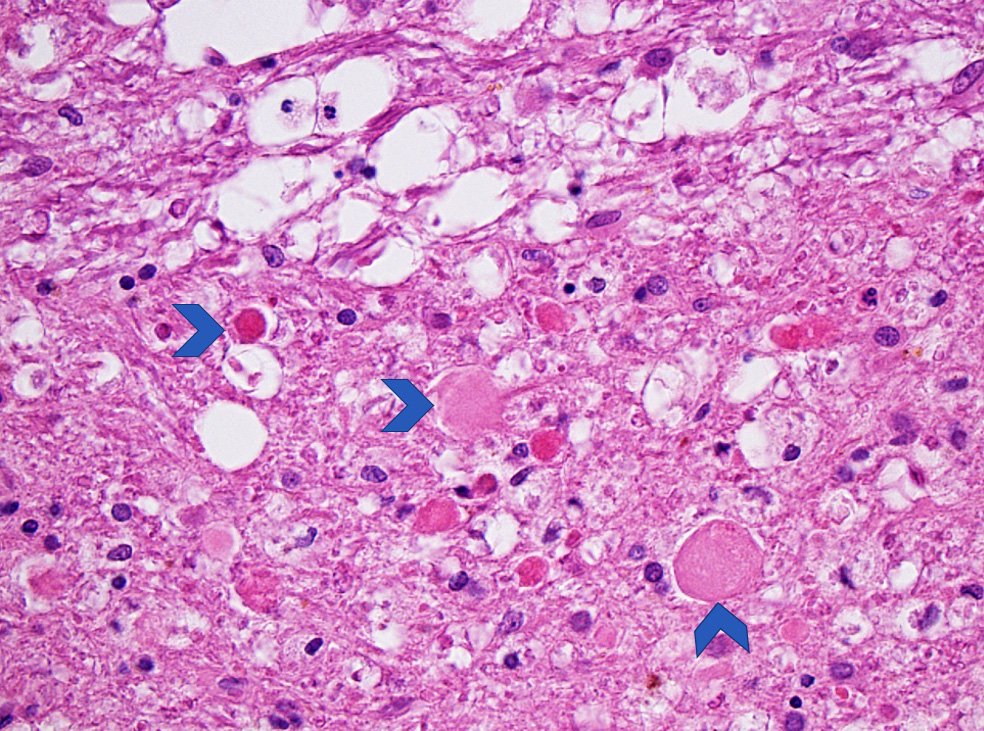

Microscopic (histologic) description

- Subacute (5 - 14 days)

- Dense macrophage infiltration and scattered siderophages

- Variable neutrophilic infiltration

- Peripheral reactive astrocytosis and microglial activation (i.e., rod shaped microglia)

- Hypereosinophilic neurons are still present in gray matter

- Neovascularization of necrotic tissue and reactive endothelial cells

- Chronic (15 days - years)

- Cavitated lesion with vessels and macrophages surrounded by a glial scar

- Reactive astrocytes in the edge of the cavitation

- Can be piloid gliosis with Rosenthal fibers, particularly in brainstem infarcts

- Scattered hemosiderin laden macrophages typically present

- Axonal balloons can occur in all phases of ischemic injury (i.e., dilation of axons indicate injury with subsequent defective axonal transport)

- Neuronal ferrugination occurs occasionally in subacute to chronic infarcts, characterized by perykaryal mineralization (i.e., prominent basophilia)

Microscopic (histologic) images